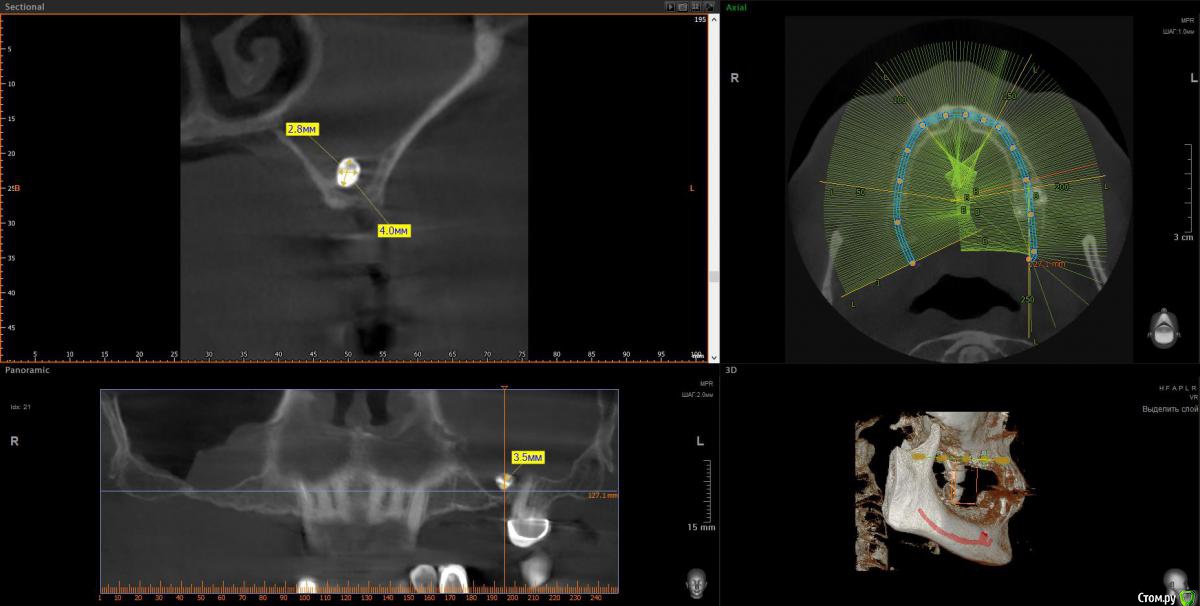

wladdX Опубликовано 9 апреля, 2018 Поделиться Опубликовано 9 апреля, 2018 Несколько скриншотов 2 Ссылка на комментарий

Irouil Опубликовано 10 апреля, 2018 Поделиться Опубликовано 10 апреля, 2018 1. Внизу справа можно имплантироваться, мягкотканную пластику провести нужно будет только 2. В пазухе слева живёт грибок, надо удалять независимо от вида имплантации на верхней челюсти 3. Про зигомы надо ещё КТ самих скул 4. С трефоилом знаком только по наслышке, но он используется (вроде бы) только на нижней челюсти, там необходимости его я не вижу. Коллеги, что знакомы с ним лучше, могут поправить. 1 Ссылка на комментарий

Irouil Опубликовано 10 апреля, 2018 Поделиться Опубликовано 10 апреля, 2018 Спасибо,уважаемые доктора,в пазухе слева дентин.Там пломбировочный материал, возможно искусственный дентин, грибковое тело растет на немА мягкотканная пластика проводится одновременно с установлением имплантов?ДаДля установки имплантов внизу справа сколько их нужно и должны ли они быть меньшего размера из-за атрофии костной ткани?Меньшего чем что? Чем Ваша челюсть? безусловно. В остальном, по моему мнению, установить Вам имплантаты с покрывающими необходимости размерами особых препятствий нет. Нужно два имплантата установить. А импланты внизу слева- сколько их нужно- один или два? С нетерпением жду ответа.Зависит от того, сколько и что будет наверху. 1-2 1 Ссылка на комментарий